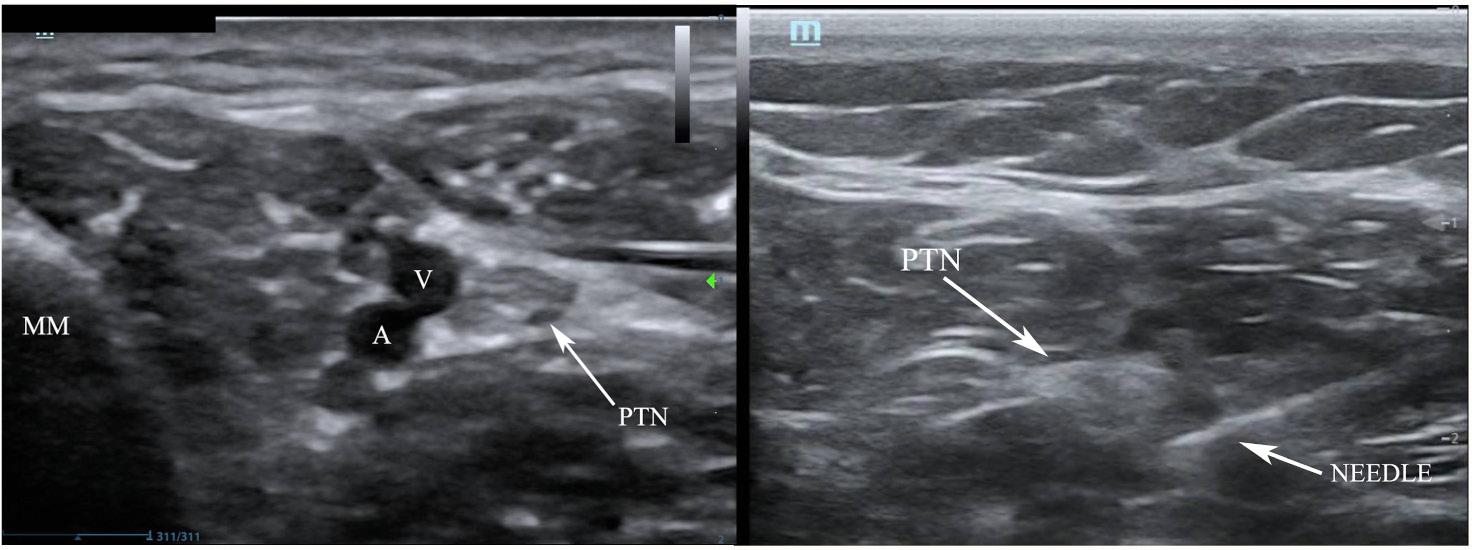

Ultrasound-guided PTN blocks were performed using the same technique for each patient (Image 3), blocking the left PTN for patient 1 and bilateral PTNs for patients 2 and 3. Using a linear transducer, the PTN was identified adjacent to the medial malleolus, keeping the posterior tibial artery and vein in view. The needle was advanced using an in-plane approach and normal saline was introduced to confirm location at the nerve and away from surrounding structures. Following conformation, five milliliters of local anesthetic was injected and observed to surround the nerve. After 10 minutes the patients were re-evaluated, and each patient reported significant improvement in their pain, all scoring 0/10 on the pain scale. The table highlights the type of local anesthetic and post-block pain scores for each patient. Successful blister debridement was performed in the ED for patients 1 and 3. Patient 2 had her burn care performed on the burn surgery service floor immediately following PTN block in the ED. There were no reports of local or systemic toxicity from the anesthetic.

Ultrasound-guided Posterior Tibial Nerve Block for Frostbite of the Plantar Surfaces Image 3. Posterior tibial nerve (PTN) block. Left demonstrates anatomical landmarks of the medial malleolus (MM), vein (V) and artery (A). Right, the needle with anesthetic spread around the PTN coming from a posterior approach.